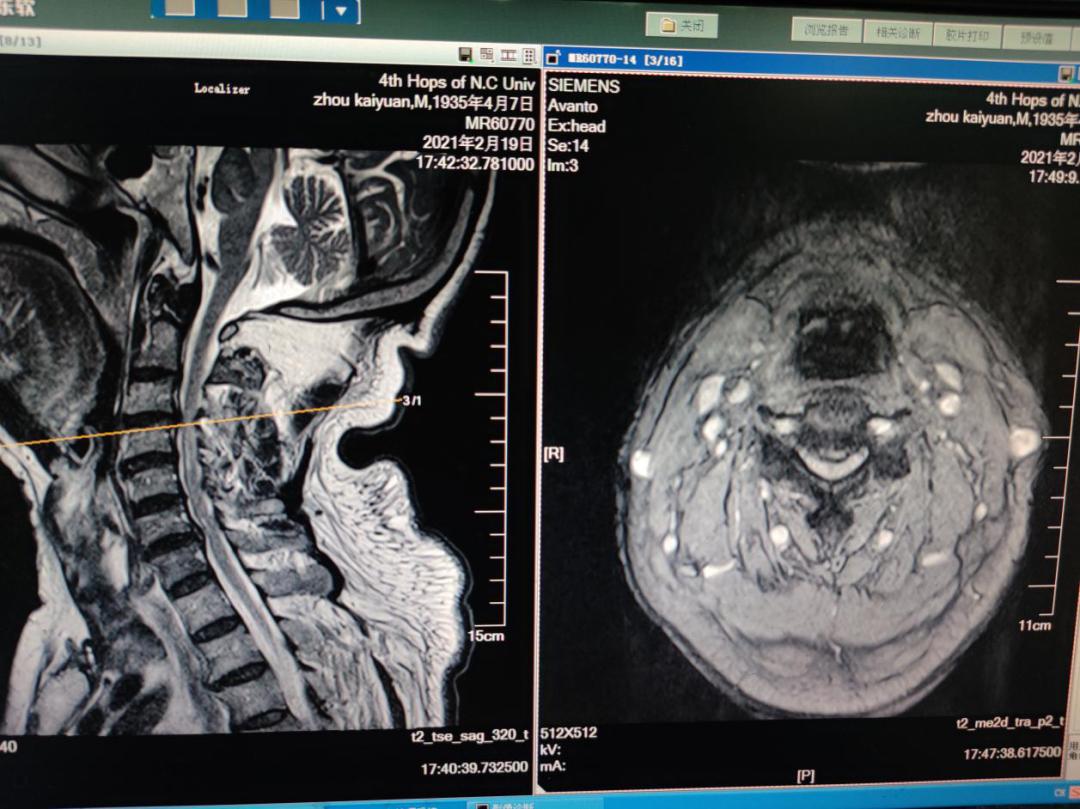

经过吴炳华教授团队诊疗后,发现患者双上肢也存在肌力下降的情况,骨科组织多学科联合会诊讨论后认为,该患者症状来源主要来自C3/4节段的脊髓受压迫造成,随即团队为患者制定精密的手术方案,成功的为患者实施了颈椎前路ACDF手术。术后麻醉苏醒后患肢及感四肢力量明显较术前增强,术后第二天患者就行走自如。

本次手术以最小的创伤,彻底切除了患者严重压迫颈脊髓的骨化韧带及突出的髓核,最大程度地保留了正常的颈椎结构。 吴炳华介绍,由于颈前部解剖结构复杂,术野很小,需要在方寸之间进行切除、松解、融合、内固定等一连串高难度技术操作。特别是颈椎区域存在血管、神经等重要结构,从技术上需要术者具备精准的解剖结构专业知识和丰富的临床手术经验,手术难度系数高。